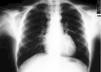

En los exámenes complementarios se evidenció una radiografía de tórax anteposterior y lateral con imagen cardíaca resaltada por la presencia de aire en mediastino hasta axila, así como aire en estructuras mediastínicas posteriores, que disecan tejido subcutáneo hasta el cuello (fig. 1 y 2). Se realizó igualmente electrocardiograma que resultó normal.

Figura 1. Imagen de aire en mediastino, resaltándose figura cardíaca con aire tras parrilla costal.